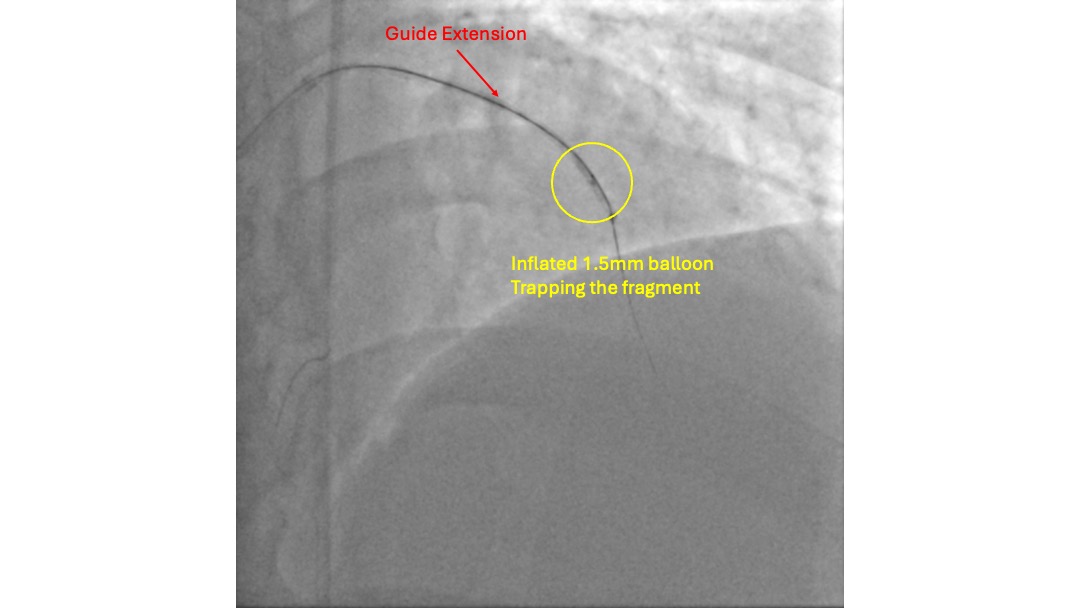

With the support of a FineCross micro-catheter (MC), the proximal CTO cap was punctured with a Gaia First wire. The wire traversed the CTO body through the intra-plaque space without much difficulty, reaching the distal lumen, which was confirmed by contralateral injection. However, the MC could not be delivered to the distal lumen over the Gaia First wire. The CTO lesion was pre-dilated with a 1.0 mm balloon, but it burst during the fourth inflation, and the MC still failed to advance. Subsequently, a trapped foreign body was noted on the distal aspect of the wire that prevented the advancement of the MC. This was initially thought to be a fragment fractured from the 1.0 mm balloon. The intervention was continued over the Gaia First wire to facilitate the removal of the fragment. The lesion was pre-dilated with a 2.5 mm non-compliant (NC) balloon and a 3.5 mm cutting balloon. Two 3.5 mm drug-coated balloons (DCBs) were then used to treat the lesion. With adequate luminal gain, an extension catheter was advanced into the LAD, and the fragment was retrieved inside it. A 1.5 mm balloon was then deployed to trap the fragment inside the extension catheter. The wire, extension catheter, and inflated 1.5 mm balloon were then removed simultaneously from the LAD. Inspection of the wire revealed that the fragment was, in fact, an unraveled coronary wire rather than a fractured balloon.